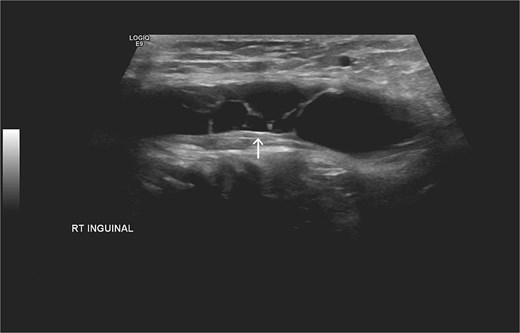

Laboratory studies, including complete blood count and comprehensive metabolic panel, were within normal limits. Initial ultrasonography (US) revealed an oblong cystic lesion with fine septations, measuring 6.5 × 3 cm, extending through the right inguinal canal into the labium majus (Figs 1 and 2). Subsequent pelvic magnetic resonance imaging (MRI) corroborated these findings, demonstrating a right lower abdominal cystic lesion with thin septations extending to the inguinal region, showing low T1 and high T2 signal intensity, measuring ~7 × 3.5 cm (Figs 3 and 4). No evidence of bowel or omental herniation was observed, suggesting canal of Nuck hydrocele.

US of the right inguinal area showing oblong cystic lesion measuring 6.5 × 3 cm, extending through the right inguinal canal into the labium majus (arrow).